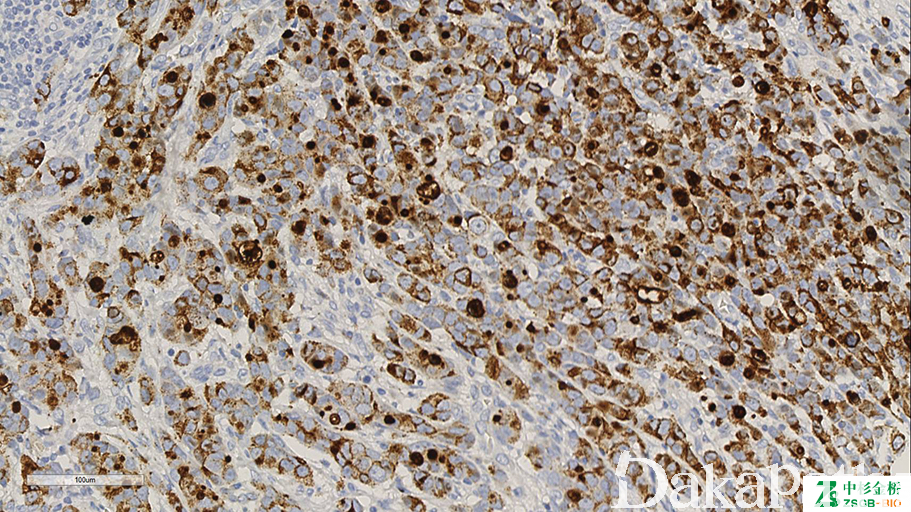

信号定位: 胞质

通常阳性(<95%,≥75%的病例阳性): 肾细胞癌、涎腺导管腺癌、乳腺浸润性癌,非特殊类型、小汗腺汗孔癌